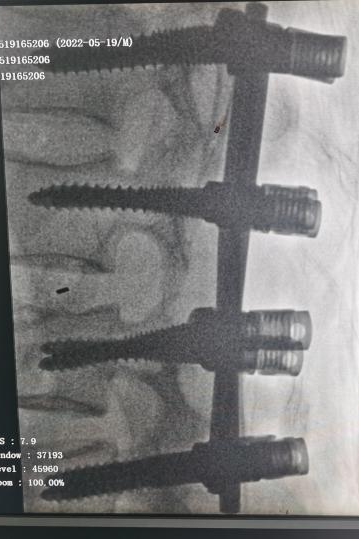

术后患者生命体征平稳,转ICU进一步支持治疗后再次送入手术室,麻醉科卢斌主任带领麻醉团队实施全麻后,骨外科2组曹炯哲团队给予行腰3椎体Chance骨折切开复位,椎板切开减压,腰2-3椎体植骨融合,椎弓根钉内固定术。随后胸外科左军涛主任带领团队给予行胸廓成型+肋骨骨折切开复位内固定+胸腔闭式引流术。手术总历时8小时。术后患者转ICU进一步生命监测及支持对症治疗。